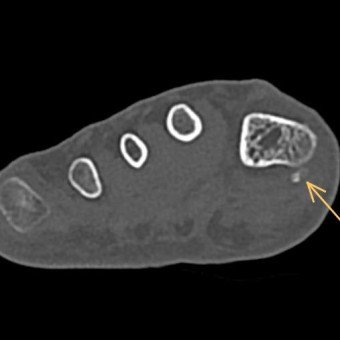

Fragliche Darstellung des Überbeines im MRI

Zur genaueren Untersuchung und Darstellung machten wir daher ein CT, das die Knochen besser darstellt.